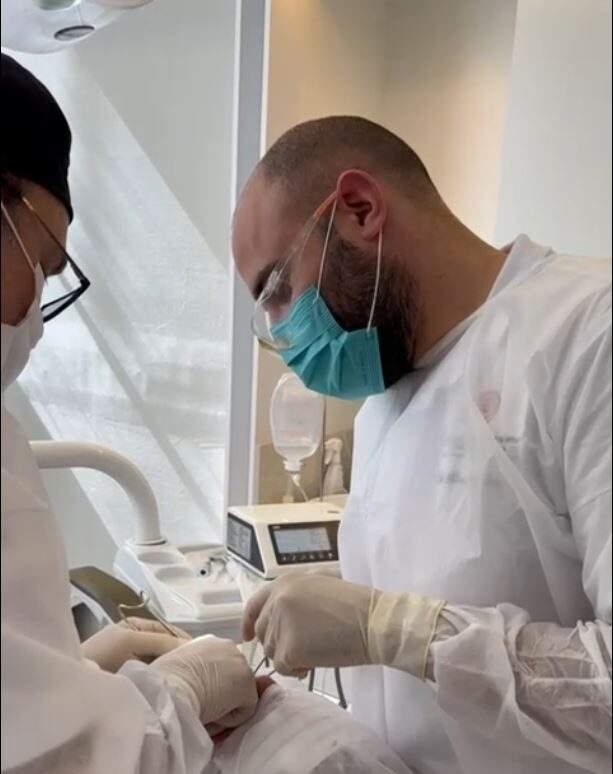

I nostri Tutor

Dott. Vincenzo Vitale

Odontoiatra, Instancabile e appassionato di chirurgia orale, è Tutor e responsabile Italiano di Cursos Internacionais di Cirurgia.

SII TU IL PRIMO OPERATORE, SEMPRE! DALL’INIZIO ALLA FINE. IL TUO ASSISTENTE SARA’ UN TUTOR DEDICATO CHE TI SEGUIRA E GUIDERA’ PASSO DOPO PASSO NELLA RISOLUZIONE DEL CASO CHIRURGICO!